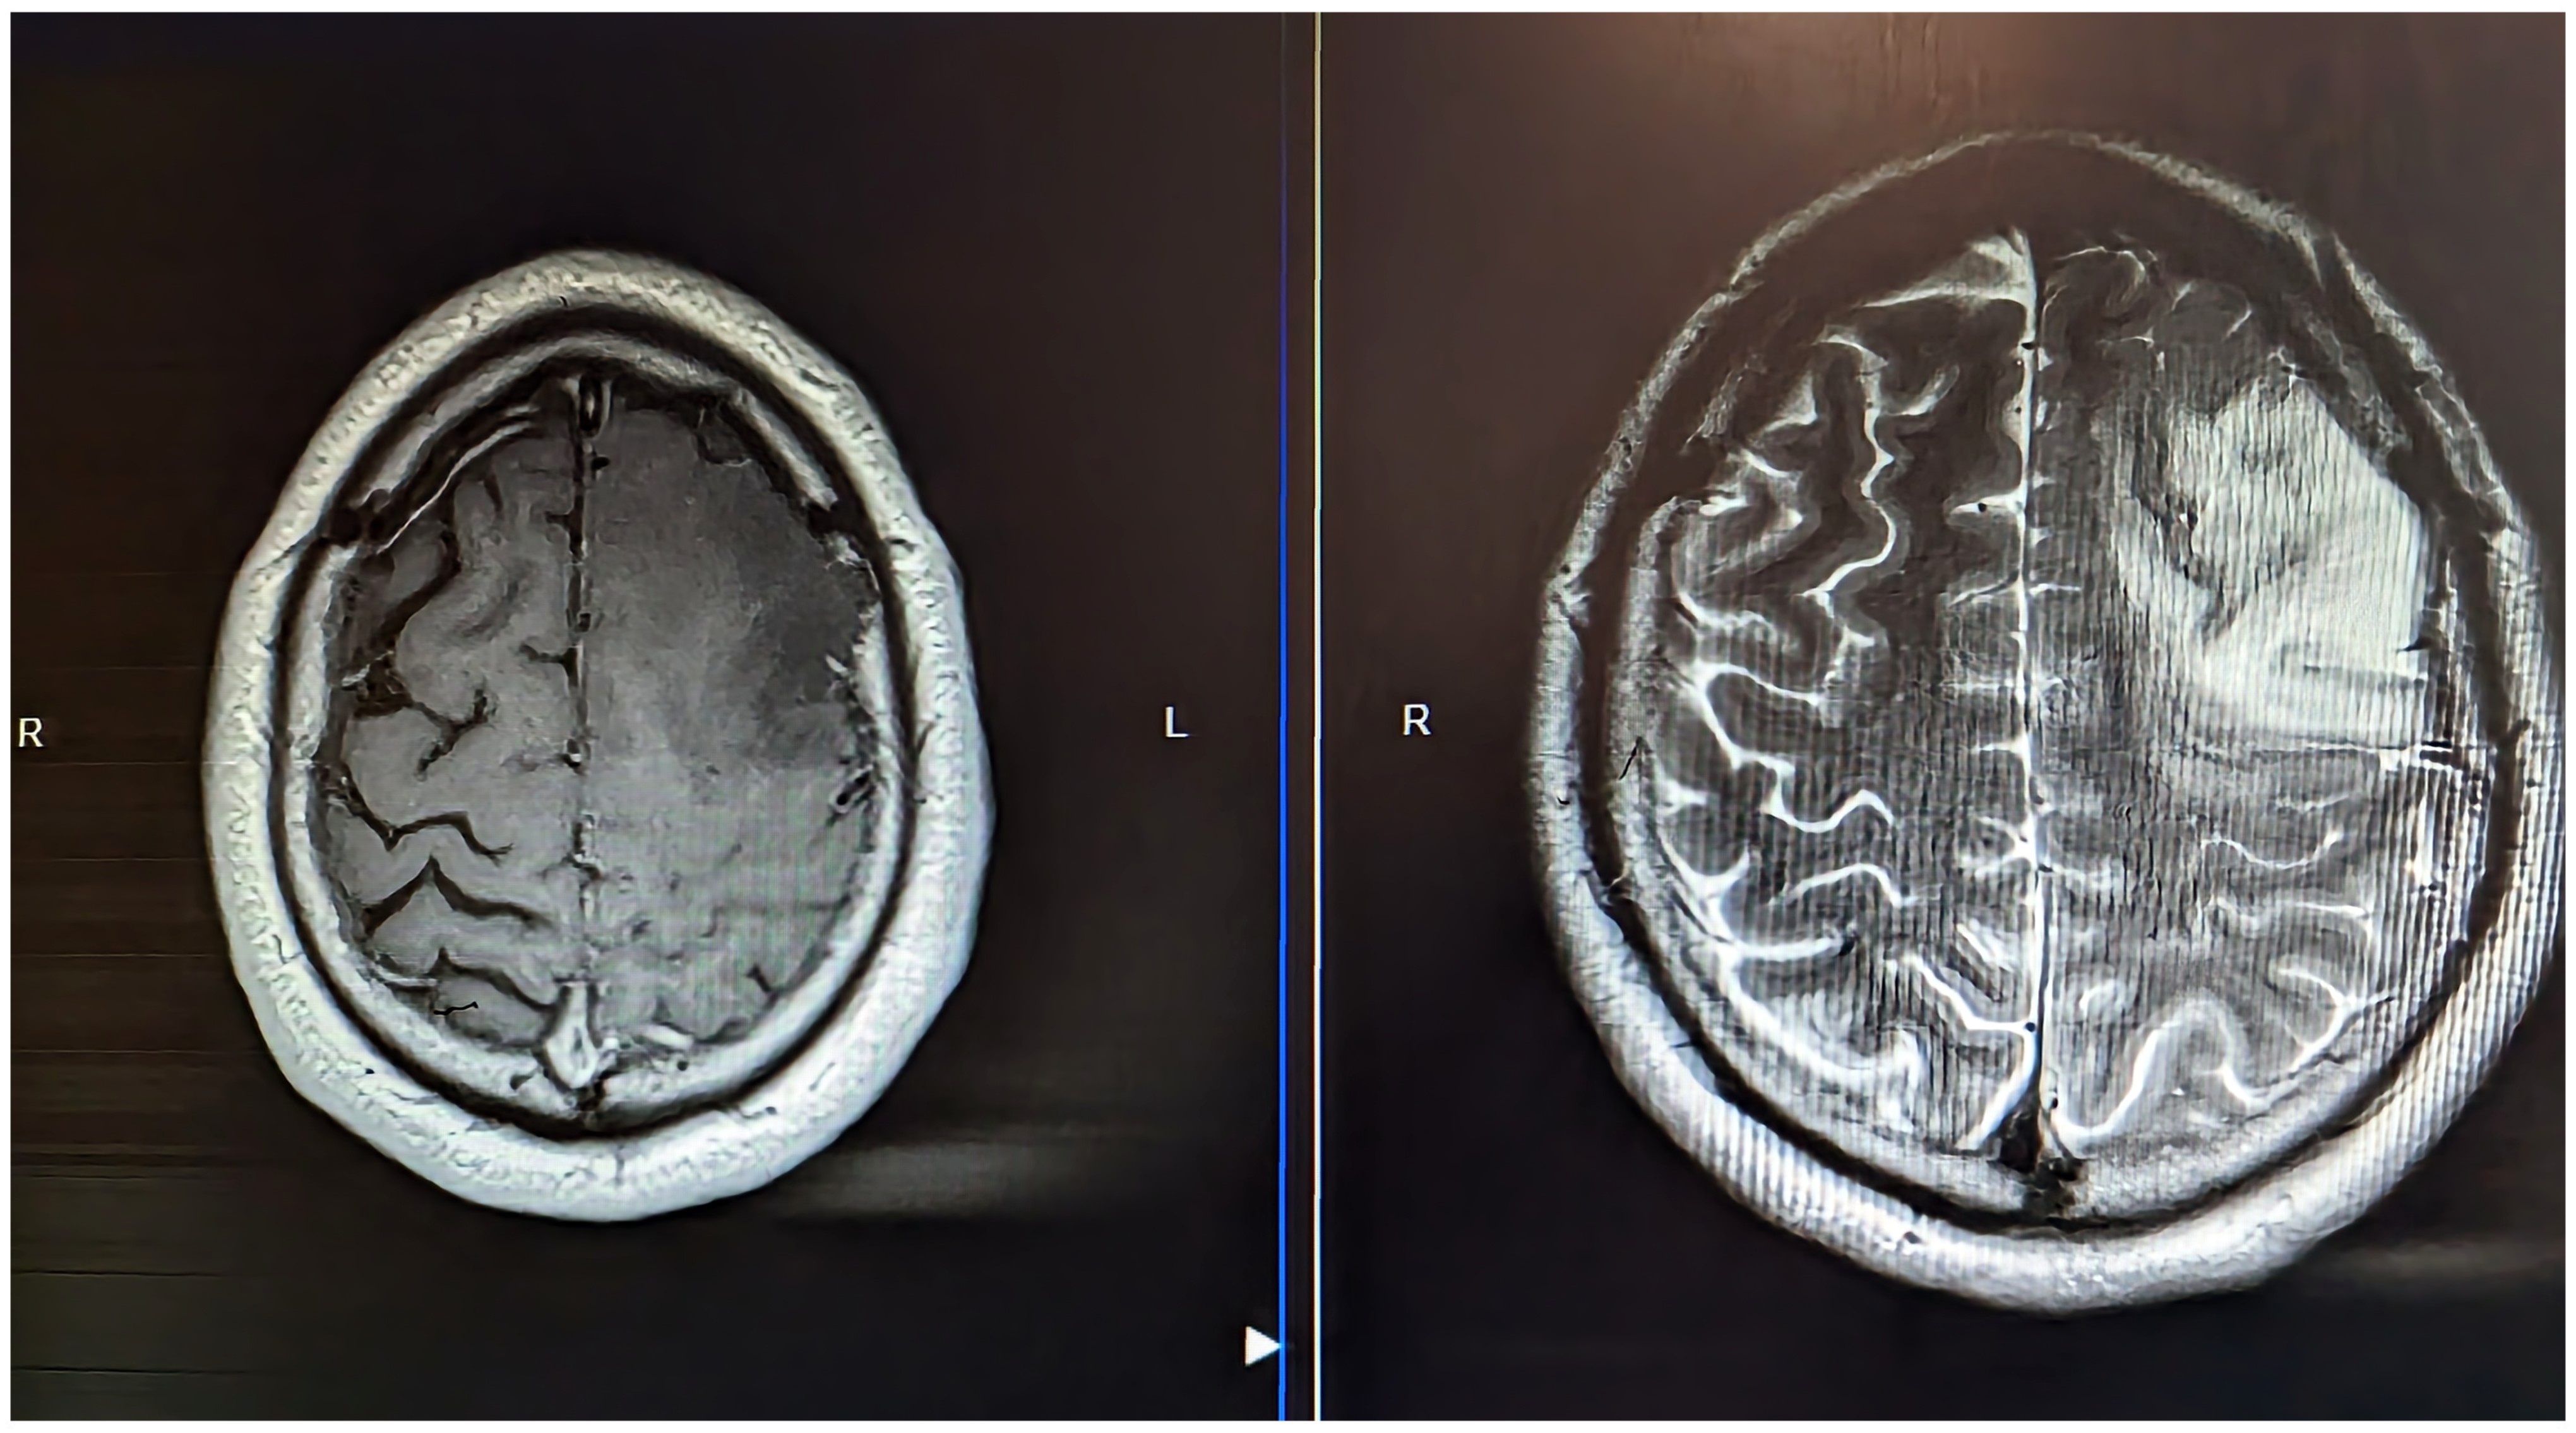

After a road traffic accident, a pear-sized Glioma–a type of brain cancer was discovered as an unexpected and unwelcome guest in my head

The Story, So far in pictures…